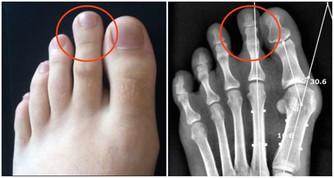

1、牙齒咬合不齊

健康的牙齒是上下配對的,這樣才能配合咀嚼。當牙齒排列不整齊時,上下牙齒之間的咬合關係發生了改變,容易造成塞牙。

建議:符合正畸治療的適應證,那麼最好去做牙齒矯正。

6、智齒

多數智齒生長方向不正常,比如它向前傾斜生長,就會與前牙形成比較大的夾角;

再者,沒有配對牙的智齒伸長,也很容易與前面一顆磨牙之間形成較大的縫隙,引起食物嵌塞。

建議:沒什麼用的智齒就拔了吧,反正也不用它咀嚼~